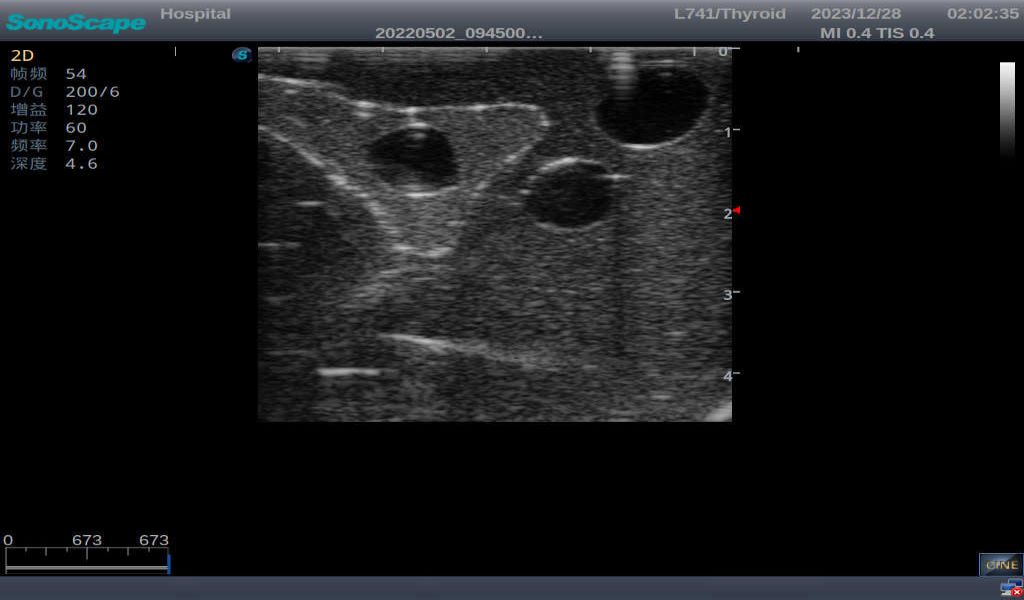

Thyroid cyst, which fluid area, dark and echo-free area can be seen